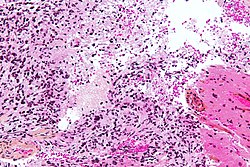

Histomorphologic comparison of common gliomas:

| Entity | Rosenthal fibres / EGBs |

Nuclear atypia | Mitoses | Necrosis | MVP | Infiltrative | Image |

| Pilocytic astrocytoma | yes | usu. no | usu. no | usu. no | yes | no | |

| Astrocytoma CNS WHO grade 2 | no | yes | no | no | no | yes | |

| Astrocytoma CNS WHO grade 3 | no | yes | yes | no | no | yes | |

| Glioblastoma | no | yes | yes | yes | yes | yes | |

| Oligodendroglioma | no | usu. no | yes | no | no | yes | |

| Ependymoma CNS WHO grade 2 | no | usu. no | usu. no | usu. no | no | discrete | |

| Ependymoma CNS WHO grade 3 | no | yes | yes | usu. yes | rare | discrete |